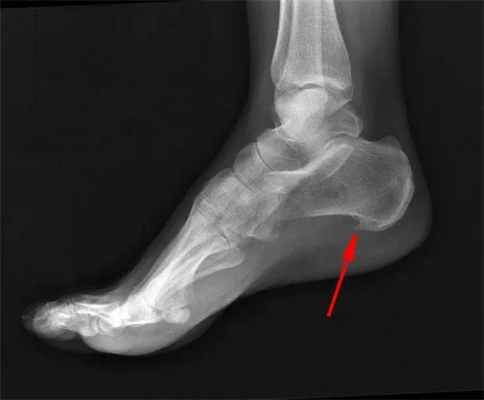

Уточнить диагноз позволяет рентгенография стопы. При этом на рентгенограмме виден костный нарост.

После консультации диагноз «пяточная шпора» подтвердился – на рентгеновском снимке костный нарост был четко виден. На приеме специалисты клиники объяснили женщине: методы, на которые она возлагала надежды, эффективны только в самом начале заболевания. А так как Наталье Борисовне пяточная шпора не один год мешает нормально жить, операция была единственным верным решением. Более того, медлить с вмешательством было ни в коем случае нельзя.

Ренген-снимок до операции Рентген стопы после операции

Диагностикой и лечением пяточной шпоры занимается врач ортопед. Основным способом выявить патологию и оценить степень ее развития является рентгенография. На снимке хорошо виден костный нарост, его форма, расположение и величина.

Пяточная шпора представляет собой депозит кальция на нижней части пяточной кости. На рентгеновском снимке, пяточная шпора может выступать вперед на 0.5-1 см. Хотя пяточные шпоры часто безболезненны, тем не менее, они могут быть причиной достаточно сильных болей. Пяточные шпоры часто ассоциированы с подошвенным фасцитом. Подошвенный фасцит является наиболее частой причиной болей в нижней части пятки. Приблизительно 2 миллиона пациентов в США лечатся по поводу подошвенного фасцита каждый год. Подошвенный фасцит возникает, когда сильная полоска ткани, которая поддерживает свод стопы (плантарная фасция), раздражается и воспаляется. Пяточные шпоры на задней части пятки нередко также ассоциированы с воспалением ахиллова сухожилия (тендинитом) и могут быть причиной болезненности и болей в задней части пятки, усиливающейся при разгибании стопы.

После изучения истории болезни, жалоб пациента, врач проводит осмотр ноги: наличие высокого свода, площадь болезненности в области пятки, наличие ограничений подвижности в стопе. Для верификации диагноза могут потребоваться инструментальные методы исследования. Рентгенография позволяет получить четкое изображение костных тканей. Это метод исследования дает возможность исключить другие причины болей в пятке,такие как перелом или артроз. Пяточная шпора хорошо визуализируется при рентгенографии.